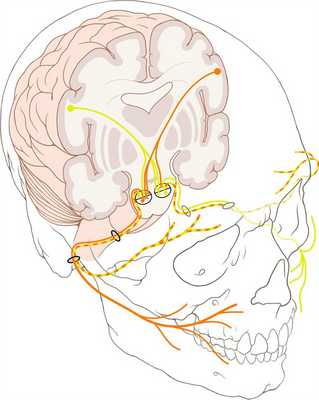

• ВМЛН: доброкачественное поражение, расположенное возле интратемпорального сегмента лицевого нерва в области ямки коленчатого ганглия

1. Общая характеристика:

• Лучший диагностический критерий:

о Поражение с гиперденсным матриксом в виде «пчелиных сот» в области ямки коленчатого ганглия (КТ в костном окне)

о Поражение в области коленчатого ганглия с накоплением контраста, неровными краями на МРТ Т1 С+

• Локализация:

о Область ямки коленчатого ганглия >> внутренний слуховой канал (ВСК)

2. КТ при венозной мальформации лицевого нерва в височной кости:

• КТ в костном окне:

о Плохо отграниченное поражение в ямке коленчатого ганглия

о Аморфные изменения костей («пчелиные соты»): отличительный признак:

- 50% всех поражений

- 100% поражений большого размера

о Возможны точечные очаги высокой плотности

3. МРТ при венозной мальформации лицевого нерва в височной кости:

• Т1 ВИ:

о Поражение со смешанной интенсивностью сигнала с очагами низкой интенсивности в матриксе (остеогенный матрикс)

• Т2 ВИ:

о Гиперинтенсивное поражение с очагами низкой интенсивности в матриксе

• Т1 ВИ С+:

о Интенсивное контрастирование является правилом

о Периневральное распространение от коленчатого ганглия:

- Кзади и латерально вдоль барабанного сегмента ЧН VII

- Кзади и медиально вдоль лабиринтного сегмента ЧН VII → ВСК:

Возможны изменения в виде «гантели»

о ВМЛН в области дна ВСК полностью имитирует вестибулярную шванному:

- Овоидное, хорошо отграниченное, контрастирующееся образование в ВСК

- Гипоинтенсивные очаги позволяют отличить ВМЛН от вестибулярной шванномы